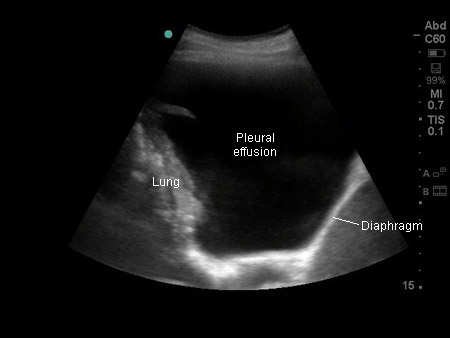

Thoracic ultrasound image of large, simple pleural effusion

From the collection of Dr Nicholas Maskell; used with permission